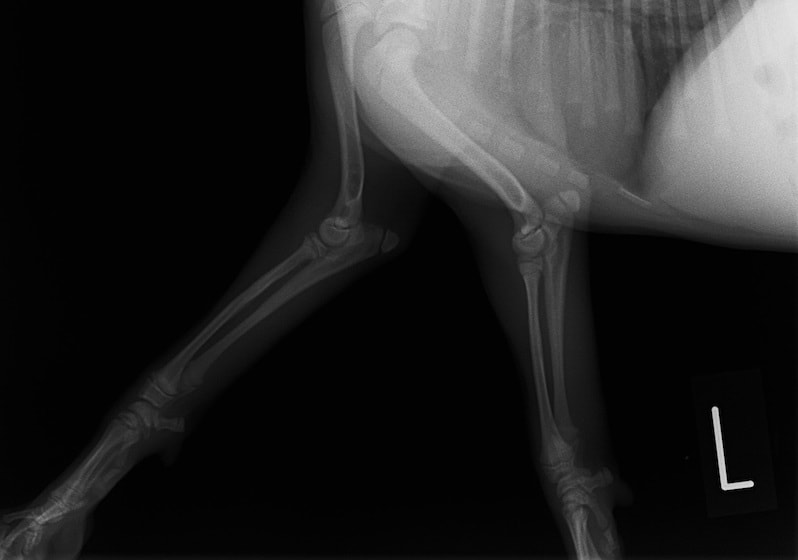

トイプードル 右遠位橈尺骨短斜骨折のALPSによる内固定

橈尺骨骨折 : 症例1 | 症例2 | 症例3 | 症例4 | 症例5 | 症例6 | 症例7

: 症例8 | 症例9 | 症例10 | 症例11 | 症例12 | 症例13 | 症例14

: 症例15 | 症例16 | 症例17 | 症例18 | 症例19 | 症例20 | 症例21